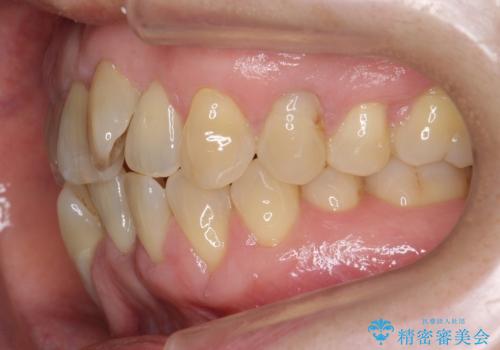

- 前歯のがたつきを主訴に来院。

右下の犬歯が歯ぐきが痩せて、歯肉退縮しておりそれを抜歯しました。

上の前歯はIPRを行なっています。

右下の犬歯の1本抜歯で最小限の抜歯で並べることができました。

奥歯も上下交互になるようにかみ合わせることができました。